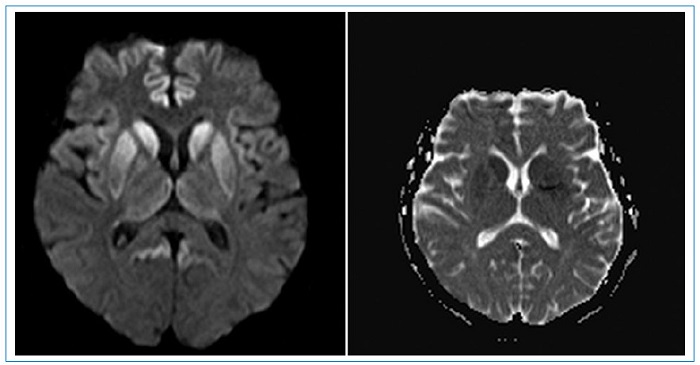

El uso de resonancia magnética (RM) en pacientes que presentan síntomas compatibles con la enfermedad aumenta la sensibilidad del diagnóstico hasta el 98%4. Los hallazgos característicos en esta consisten en hiperintensidad de la corteza cerebral y/o núcleos de la base, especialmente caudado y putamen. También se ha descrito el signo del pulvinar, que consiste en un aumento de señal simétrico en ambos núcleos pulvinares del tálamo con respecto a la corteza cerebral y la parte anterior del putamen; sin embargo, se pueden presentar falsos positivos. Otro signo descrito es el signo del “palo de hockey”, en el cual se observa un compromiso de los núcleos dorsomediales y pulvinares del tálamo3,4,5,6,7.

Se llegó al diagnóstico gracias a los hallazgos imagenológicos donde se pueden detallar los signos más comunes encontrados y descritos de la enfermedad en la literatura (hiperintensidad de los núcleos de la base, restricción a la difusión de los núcleos de la base, la corteza frontal y el giro del cíngulo y signo del “palo de hockey”) (Figs. 1,2y3), que junto con la clínica de la paciente y hallazgos en el EEG permitieron realizar el diagnóstico de ECJ.

En nuestro caso, los principales criterios diagnósticos fueron: el deterioro neurológico rápidamente progresivo, dos manifestaciones clínicas (mioclonías, compromiso de la vía piramidal), hallazgos típicos del EEG y de la RM cerebral, tratándose entonces de un caso probable de la enfermedad. Dentro de los diagnósticos diferenciales por RM están: enfermedad de Gerst mann-Sträussler-Scheinker2, encefalitis autoinmune, desmielinización osmótica, lesión cerebral hipóxica/ anóxica, encefalopatía hepática, encefalopatía hipoglucémica y enfermedad mitocondrial.